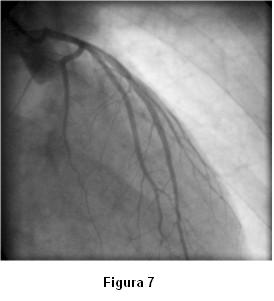

Antes de la finalización del estudio de la coronaria izquierda reitera espasmo (figura 6) que mejora sin necesidad de administración de vasodilatadores (figuras 7 y 8).